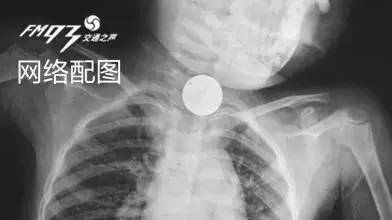

由于孩子才9个月大,食管还很狭窄,估计是硬币卡住引起疼痛,才会导致哭闹不止,鉴于情况危急,消化内镜中心医生立即决定为其行无痛胃镜取异物术。

当胃镜管进入时,发现硬币正好横着躺在喉咙处,硬币在喉咙壁经过摩擦已经变得十分红肿,随后经过麻醉师、医生、护士等一系列人员的努力,经过短短3分钟,卡在其喉咙处的硬币被顺利取出。